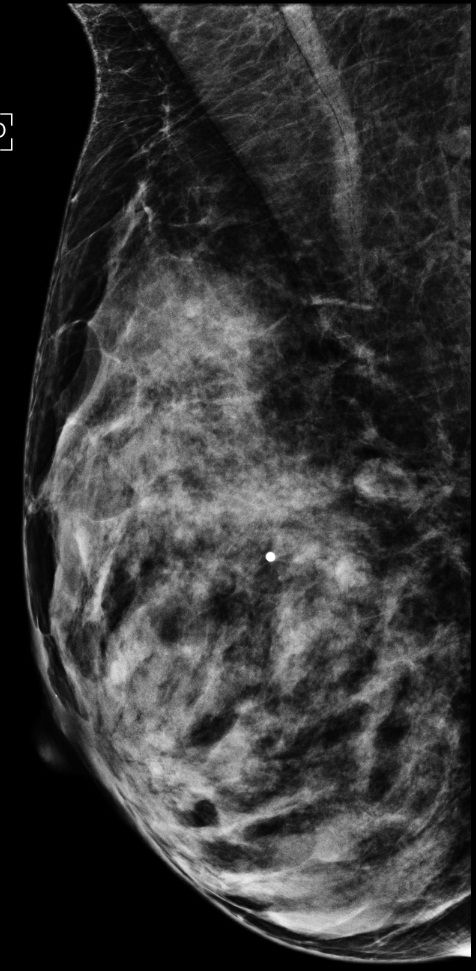

74-year-old presents with palpable lump in left breast, status post left lumpectomy for infiltrating ductal carcinoma with sequential radiation 16 years ago.